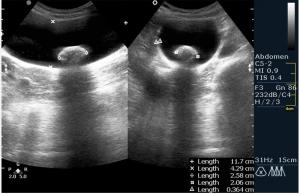

По всей видимости пузырь увеличен, напряжен, содержимое 2 крупных конкремента,один из которых вклинен.

Доктор Марио! Фиксированный камень шейки желчного пузыря. Еще один камень в просвете. Не знаю, употребляете ли Вы такой термин, но я бы еще сказал "водянка желчного пузыря". Показание к оперативному лечению желче-каменной болезни. Симптома "трехслойности стенки" не увидим. Пузырь перерастянут. Кстати, в последнее время встречается все большее и большее количество случаев желче-каменной болезни у пациентов молодого возраста. От 18 лет.

Вы совершенно правы, это холецистолитиаз с вклинённым камнем шейки (impacted GB neck stone) с перерастяжением пузыря, или водянка (GB Hydrops). Сегодня была успешнo оперирована.